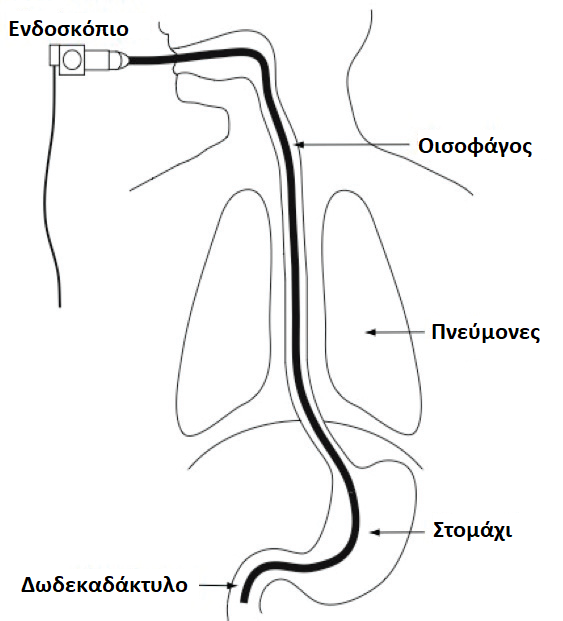

Με τη γαστροσκόπηση εξετάζεται το εσωτερικό τμήμα (αυλός) του ανώτερου πεπτικού συστήματος με τη χρήση ενός εύκαμπτου ενδοσκοπίου εξοπλισμένου με μια μικροσκοπική κάμερα.

Αναλυτικότερα, η γαστροσκόπηση επιτρέπει την εξέταση του οισοφάγου, του στομάχου και του πρώτου τμήματος του δωδεκαδακτύλου (βολβός και 2η μοίρα) (εικόνα 1).

Ο ενδοσκόπος χρησιμοποιεί έναν εύκαμπτο σωλήνα, το γαστροσκόπιο, λεπτότερο από τον δείκτη του χεριού σας (3 χιλ.), για τη διενέργεια της εξέτασης.

Μετά τη χορήγηση της μέθης, ο γαστρεντερολόγος ξεκινάει την εξέταση. Το εύκαμπτο ενδοσκόπιο προωθείται από το στόμα του ασθενούς στον οισοφάγο και μετά στο στομάχι και στο δωδεκαδάκτυλο. Ο ιατρός εξετάζει τον βλεννογόνο τόσο κατά την είσοδο όσο και κατά την απόσυρση του ενδοσκοπίου. Δεν επηρεάζεται καθόλου η αναπνευστική οδός και δεν προκαλούνται προβλήματα στην αναπνοή. Το ενδοσκόπιο έχει στην άκρη του μια πηγή φωτός και το έντερο διατείνεται με διοξείδιο του άνθρακα (CO2), για την καλύτερη εξέταση του πεπτικού σωλήνα. Η διάρκεια της εξέτασης κυμαίνεται από 10 έως 20 λεπτά.